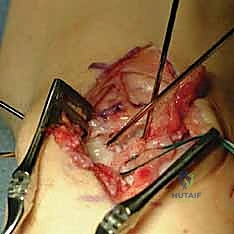

The exposure of the dorsal capsule reveals the transverse fibers of the dorsal radiocarpal (DRC) and dorsal intercarpal (DIC) ligaments. To expose the scapholunate interval while preserving tissue for a subsequent capsulodesis, we design an ulnar-based, ligament-sparing capsular flap. The incision begins radially along the dorsal rim of the radius, extends distally along the axis of the scaphoid, and then turns ulnarly, running parallel to the distal margin of the DIC ligament.

Here, the exposure highlights the ulnar-based dorsal capsular flap. The DIC parallels the transverse limb of the flap. The scaphoid, lunate, and triquetrum are clearly visualized beneath the reflected tissue.

This ulnar-based flap is carefully elevated off the underlying carpus, preserving its vascularity and structural integrity. It is imperative that this flap is at least 1 cm wide and of sufficient length to reach the distal pole of the scaphoid later in the procedure.